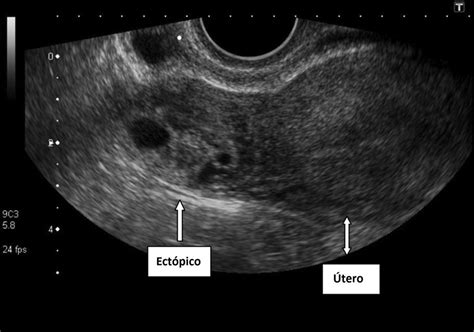

Ecografía

Gracias a los avances tecnológicos, es posible diagnosticar un embarazo ectópico en etapas cada vez más precoces mediante ecografía, idealmente con sonda vaginal y un ecógrafo de alta resolución. Signos sospechosos incluyen un útero vacío con endometrio grueso, la presencia de un seudosaco intrauterino, el signo del «doble halo» en la trompa, o la visualización de un saco gestacional fuera del útero con vesícula vitelina e incluso embrión. La visualización de una gestación intrauterina prácticamente excluye el embarazo ectópico, aunque la coexistencia de una gestación intrauterina y un embarazo ectópico (gestación heterotópica) es posible, especialmente con tratamientos de fertilidad.